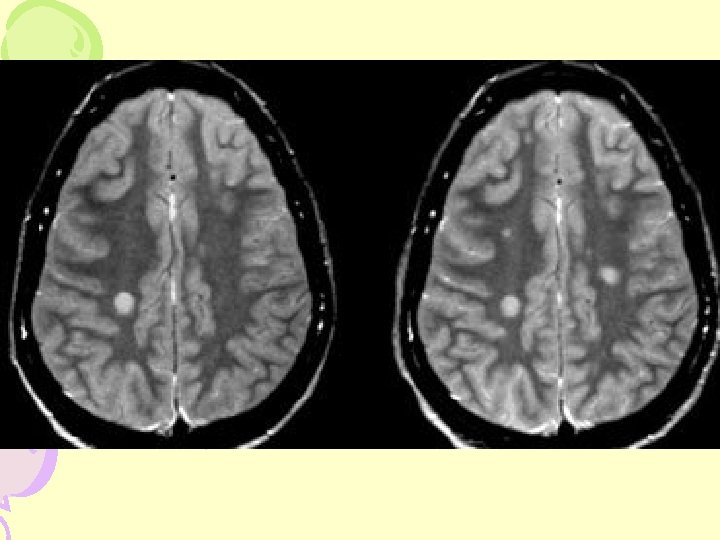

MRI- Cerebral Hemisphere

JUXTACORTICAL